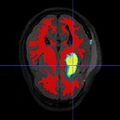

Image:New_data_p4_2.png|Segmentation result of a new subject (Z view)